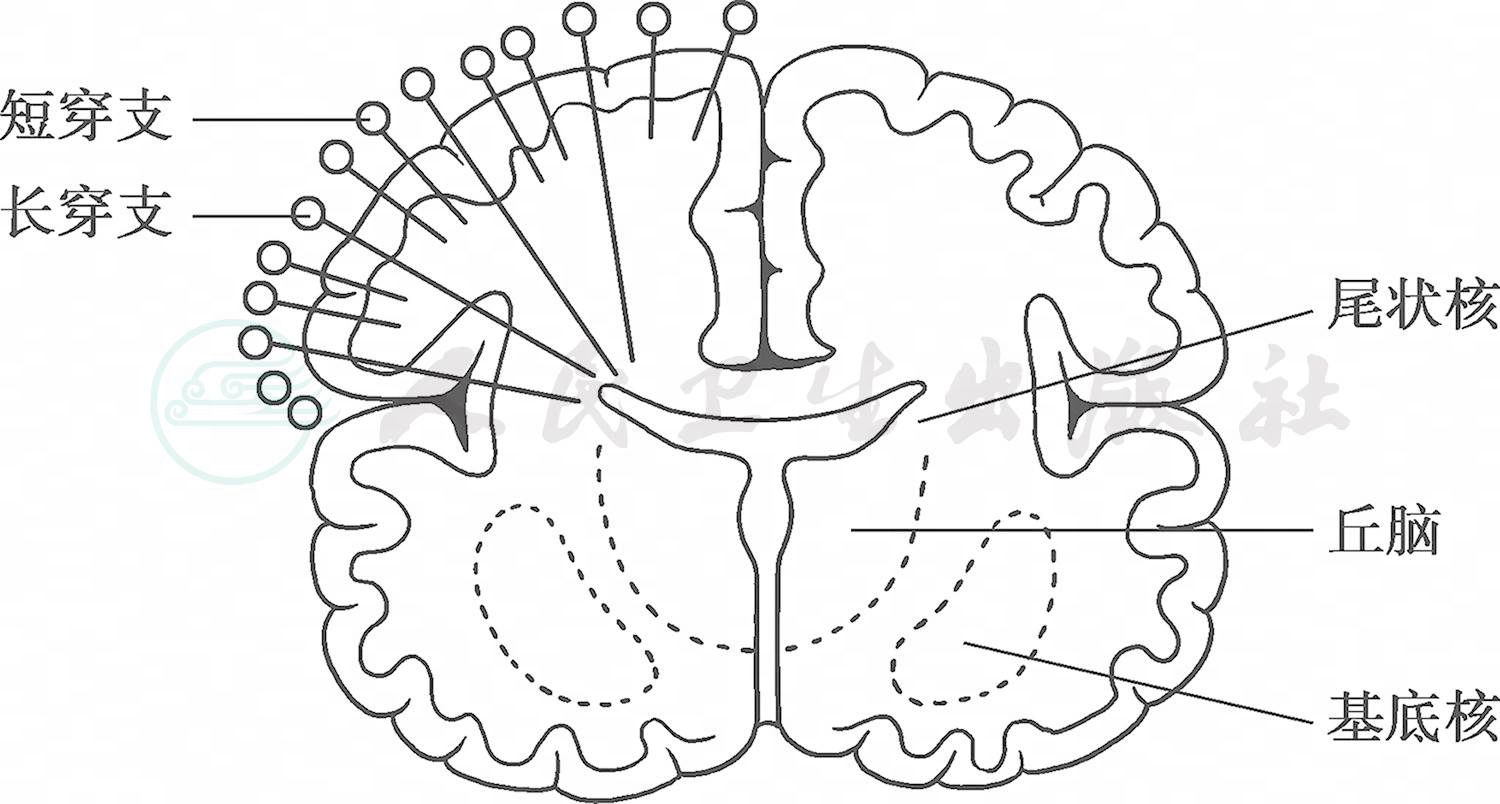

1.血管发育特点

早产儿脑血管发育不完全。从大脑前、中、后动脉发出的长穿支在妊娠24~28周出现,延伸到脑室的边缘,保证脑室周围深部白质的供血,早期在脑室周围形成血管化减少的区带。妊娠32~40周,是短穿支发育最活跃的时期,满足皮层下白质的血液供应。长穿支与短穿支间的吻合支在妊娠32周后才开始逐渐形成(图1)。由此可知,早产儿生后的一段时间内,供应白质血液的小血管在组织解剖结构上并未完全发育成熟,在功能上脑血管自主调节能力差,维持“压力被动性血流”的特点,在缺氧、低血压、低碳酸血症等疾病状态下,脑血流、脑灌注减少,脑白质容易发生缺血性损伤。

图1脑白质的血液供应

引自:实用新生儿学.第5版.ISBN:978-7-117-27403-6.主编: